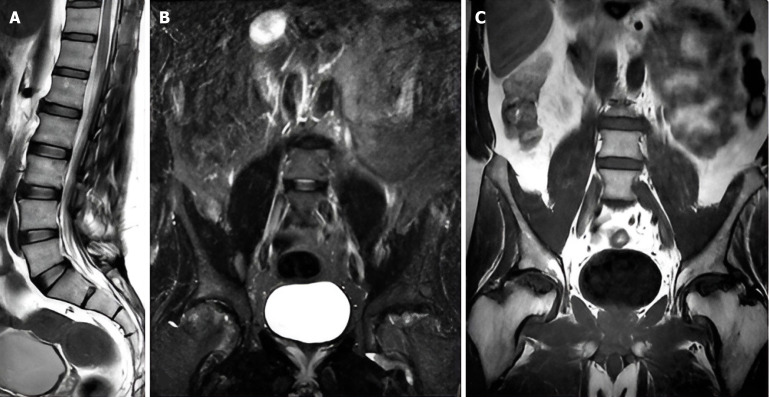

Background: Back pain and sciatica are common complaints that often require imaging for accurate diagnosis and management. Conventional lumbar magnetic resonance imaging (MRI) protocols typically include sagittal and axial T1 and T2 sequences; however, these may miss certain pathologies. The addition of coronal short tau inversion recovery (STIR) sequences offers the potential to enhance the detection of both spinal and extra-spinal abnormalities, thereby improving clinical decision-making and patient outcomes.

Aim: To evaluate the impact of adding coronal STIR sequences to routine lumbar MRI in diagnosing back pain and sciatica.

Methods: We prospectively analyzed data from patients aged 6 and older presenting with back pain or sciatica who underwent lumbar spine MRI at our institution. The standardized MRI protocol utilized included sagittal and axial T1 and T2 sequences, complemented by a coronal STIR sequence. Data on structural abnormalities were collected, reviewed, and analyzed using counts, percentages, and Fisher's exact test for categorical variables.

Results: Our cohort comprised 274 patients (115 males, 159 females; mean age 44.91 years). Notably, 39 patients exhibited abnormalities across all sequences, while 72.63% showed normal findings on the coronal STIR sequence. Importantly, 30.29% of cases were diagnosed as normal without the coronal STIR, and 36 patients with normal T1 and T2 sequences presented abnormalities on the coronal STIR. The coronal STIR sequence successfully identified 26 spinal and 10 non-spinal pathologies, including 17 cases of sacroiliitis, with a significant association (P < 0.0001) between sacroiliitis diagnosis and abnormalities visible solely on this sequence.

Conclusion: Integrating coronal STIR into routine lumbar MRI enhances detection of hidden spinal and extra-spinal pathologies, improves patient management, and offers a cost-effective, practical upgrade with significant diagnostic and clinical value.